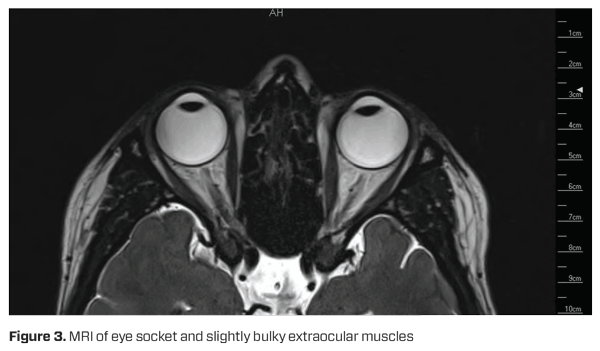

Cover test while wearing CLs found esophoria at distance and near, with a magnitude of 9 prism dioptres (PD) and 19 PD, respectively. Spectacle refraction results were R -5.00/-1.25×100 VA 6/6- and L -5.00/-0.75×65 VA 6/6- with 6 base out (BO) PD split to neutralise intermittent esotropia. Stereopsis was 200 seconds of arc. Fundus examination was unremarkable (Figure 1).

Staphyloma prevalence increases with axial length, however they may still be present in eyes with axial lengths below 26.5mm.8 In this case, interestingly, the patient had normal axial lengths and the absence of a posterior staphyloma on fundus examination (Figure 1) as well as an absence of equatorial staphyloma on MRI (Figure 3), therefore ruling out KES and HES as potential diagnoses.